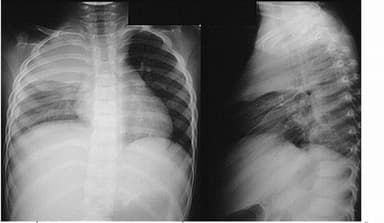

Tràn dịch màng phổi là tình trạng tích đọng dịch vượt quá mức cho phép của khoang màng phổi với các triệu chứng lâm sàng như: Đau ngực âm ỉ vùng ngực, đau nặng về phía bên tràn dịch, ho khan, ho ngày một gia tăng, sốt, nếu chụp X-quang phổi sẽ thấy hình mờ đậm, có khi mờ ở cả 2 bên phổi, tim bị đẩy sang bên đối diện.

Những biện pháp lâm sàng thường khó xác định bệnh, cần dựa vào kỹ thuật cận lâm sàng như chụp X quang, siêu âm hoặc chọc dò.

Chụp X quang là kỹ thuật hình ảnh giúp phát hiện tràn dịch màng phổi chính xác